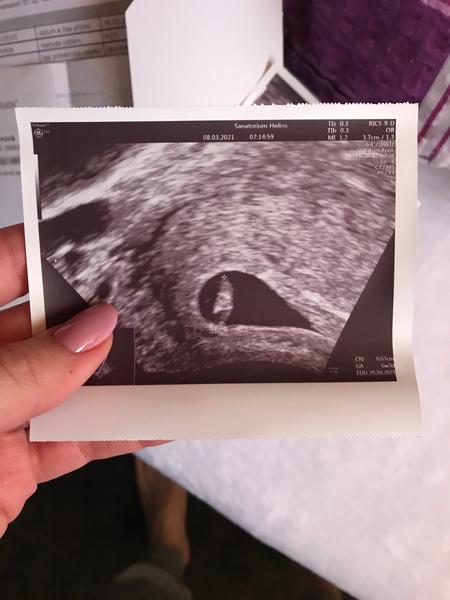

@dena99 a vis presne kdy byla ovulace? Mohla byt posunuta, proto muze byt tehotenstvi pozdejsi☺️ Ja bych zbytecne neplasila a pockala na vysledky. Ja byla u dr 6+3 a videl embryo a uz jsme slyseli i srdicko. Ale nekomu se ukaze pozdis nekomu driv😊 budu drzet palce a dej vedet jak si dopadla. Tady je muj utz z 6+3 jestli mas taky.